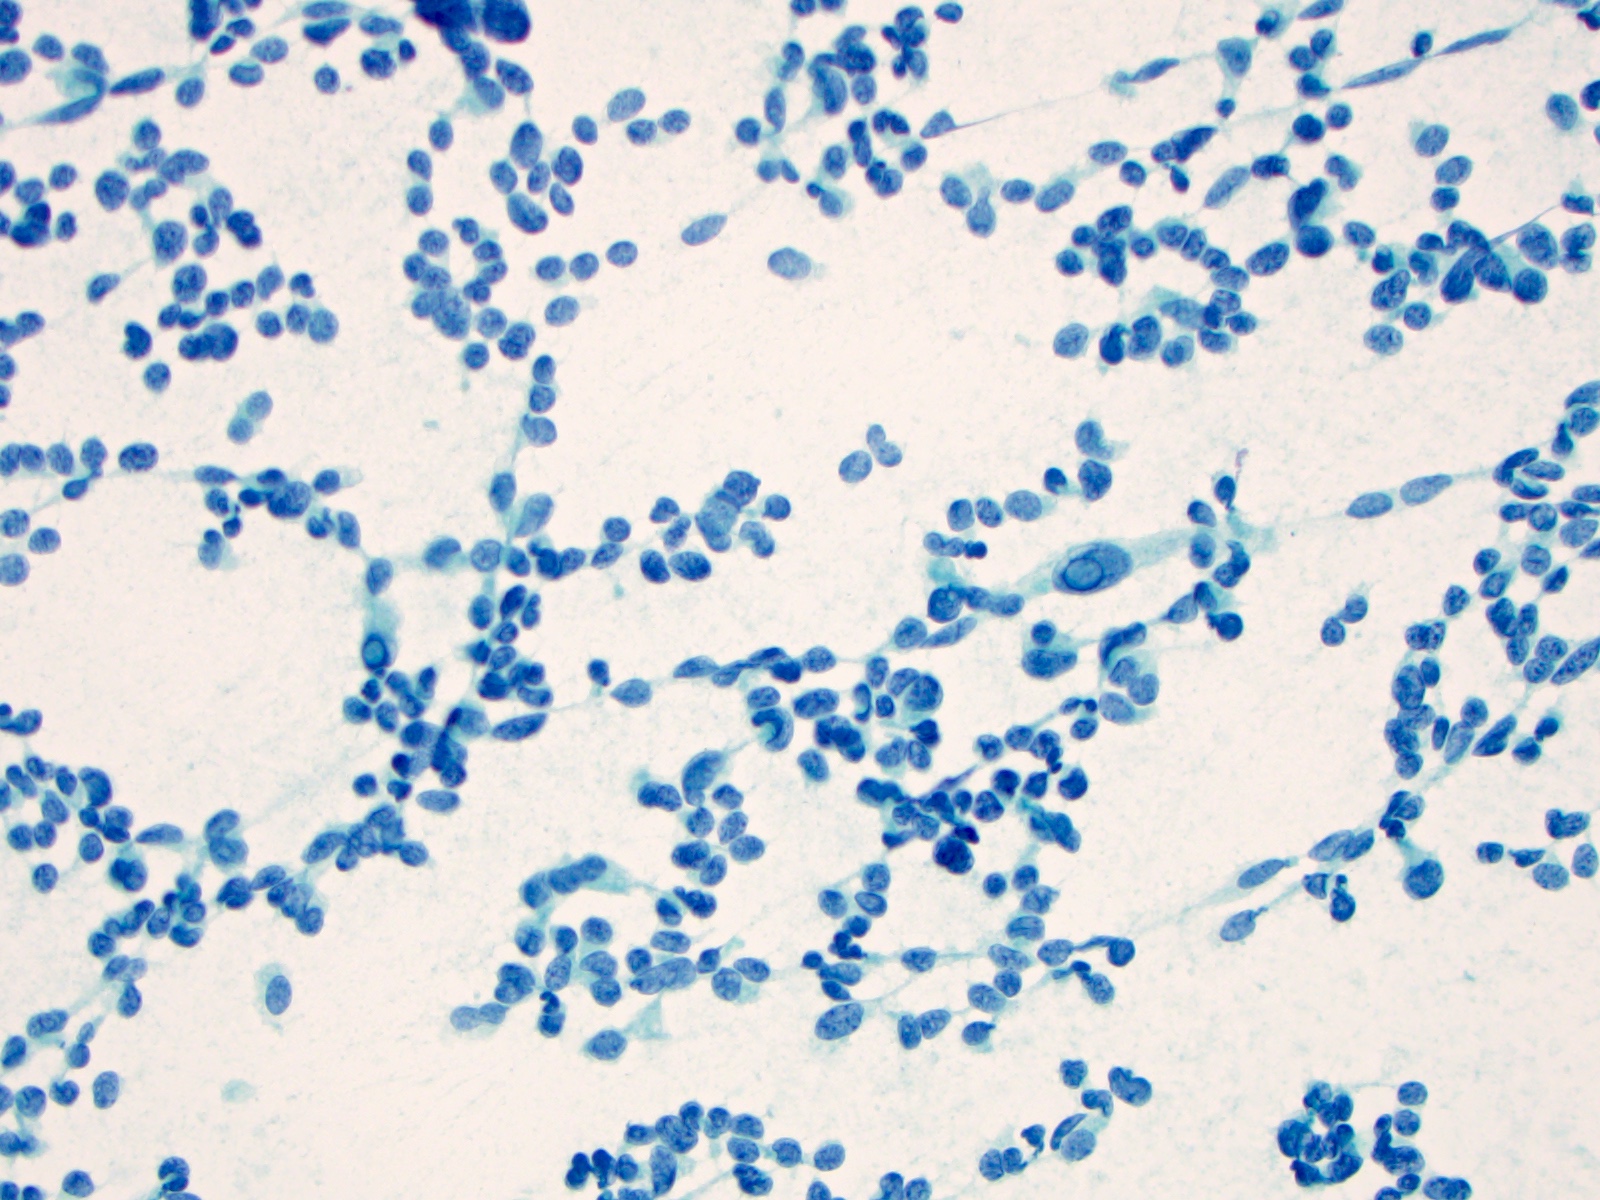

Cytology description

- Cellular specimen with round, ovoid, plasmacytoid or spindle cells singly or in small cluster; cells have abundant cytoplasm and eccentric nuclei; chromatin has salt and pepper appearance

- May have pink azurophilic granules and intranuclear pseudoinclusions; amyloid present occasionally (Am J Clin Pathol 1984;82:552)

- Paraganglioma-like variant:

- Predominantly ovoid to spindled epithelial cells in cohesive three dimensional clusters with sharp margins, rare isolated individual cells, no background colloid or amyloid

- Tumor cells have inconspicuous cytoplasm, significant nuclear atypia with occasional bizarre or binucleated cells, coarse and granular nuclear chromatin with occasional grooves and intranuclear inclusions (Cytopathology 2009;20:188)

Cytology images

Contributed by Ayana Suzuki, C.T. and Shuanzeng Wei, M.D., Ph.D.